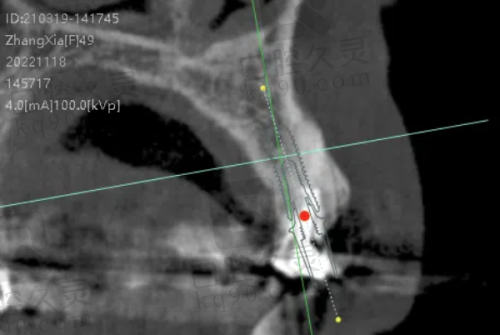

它家与多个国外种植体品牌有合作(登腾、美格真、Bego等),可供选择空间较大。同时备有CBCT三维扫描设备,更利于精细植入。